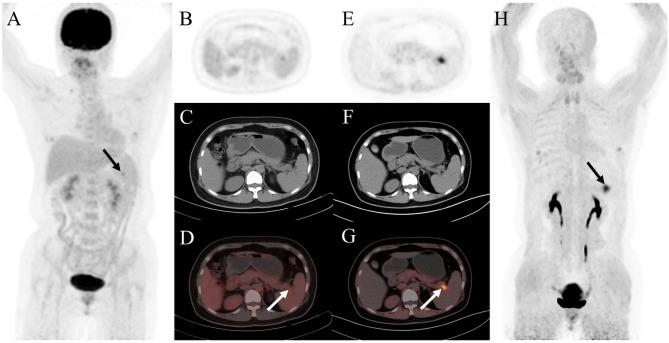

Ga-FAPI (fibroblast activation protein inhibitor) is a novel and highly promising radiotracer for PET/CT imaging. It has shown significant tumor uptake and high sensitivity in lesion detection across a range of cancer types. We aimed to compare the diagnostic value of Ga-FAPI and F-FDG PET/CT in common gynecological malignancies.

Thirty-five patients (median age, 57 years [interquartile range], 51-65 years) were evaluated. In treatment-naive patients (n = 27), Ga-FAPI PET/CT led to upstaging of the clinical TNM stage in five (19%) patients compared with F-FDG PET/CT. No significant difference in tracer uptake was observed between F-FDG and Ga-FAPI for primary lesions: breast cancer (7.2 vs. 4.9, P = 0.086), ovarian cancer (16.3 vs. 15.7, P = 0.345), and cervical cancer (18.3 vs. 17.1, P = 0.703). For involved lymph nodes, Ga-FAPI PET/CT demonstrated a higher SUV for breast cancer (9.9 vs. 6.1, P = 0.007) and cervical cancer (6.3 vs. 4.8, P = 0.048), while no significant difference was noted for ovarian cancer (7.0 vs. 5.9, P = 0.179). Furthermore, Ga-FAPI PET/CT demonstrated higher specificity and accuracy compared to F-FDG PET/CT for detecting metastatic lymph nodes (100% vs. 66%, P < 0.001; 94% vs. 80%, P < 0.001). In contrast, sensitivity did not differ significantly (97% vs. 86%, P = 0.125). For most distant metastases, Ga-FAPI exhibited a higher SUV than F-FDG in bone metastases (12.9 vs. 4.9, P = 0.036).

Ga-FAPI PET/CT demonstrated higher tracer uptake and was superior to F-FDG PET/CT in detecting primary and metastatic lesions in patients with common gynecological malignancies.